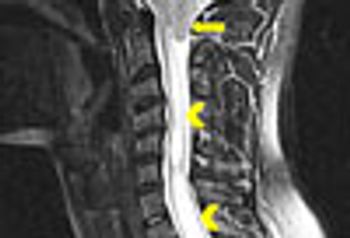

A 4-year history of headache and severe neck pain led to a diagnosis of Chiari I malformation in this patient. Here: symptoms, diagnostic tests, and treatment approaches.